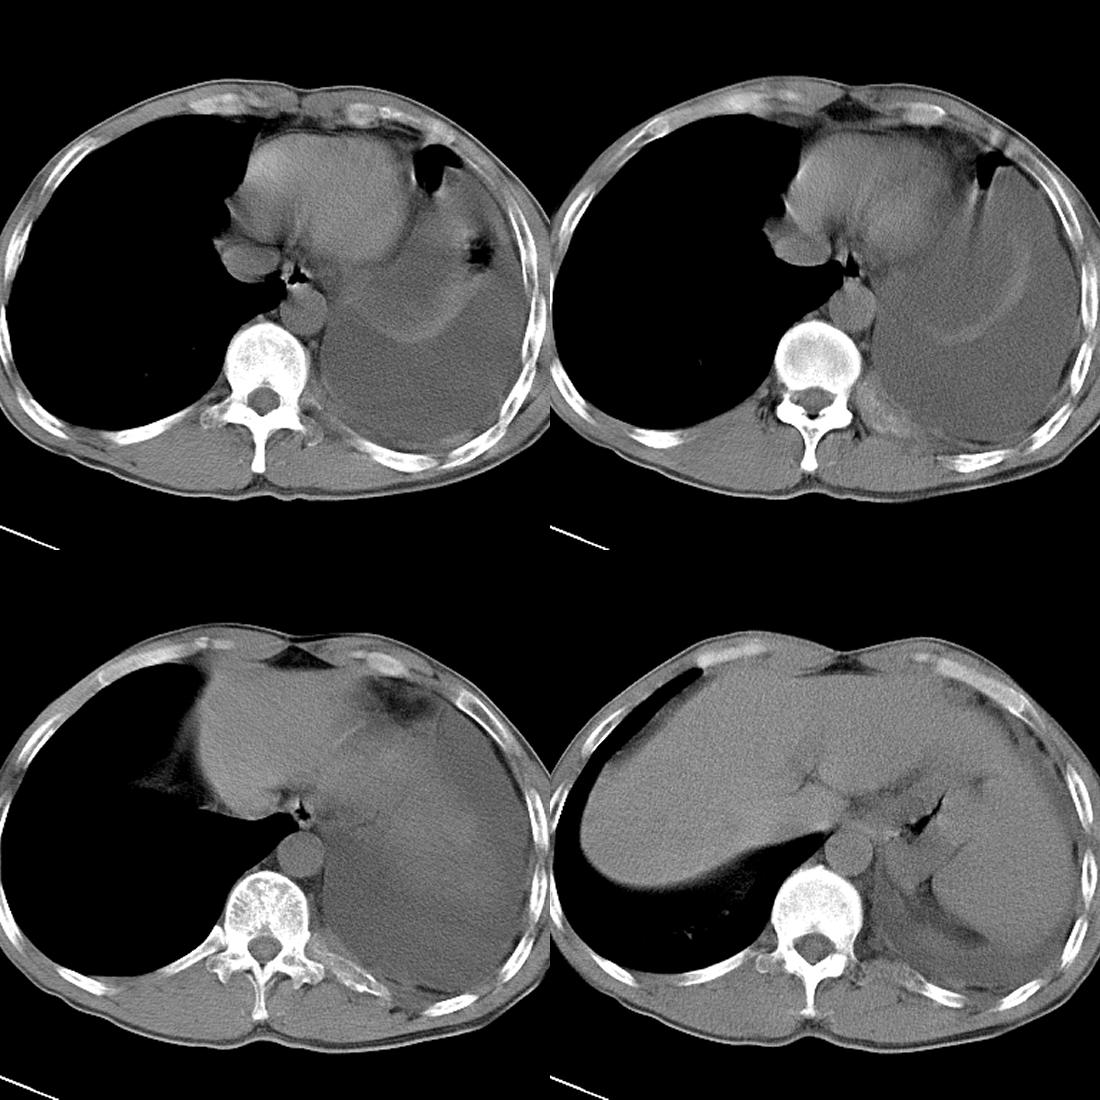

m42y,反复胸背痛数月。无明显的咳嗽、咯痰、咯血症状。

左肺上叶周围型肺癌伴肺\\胸膜\\肋骨\\胸椎横突转移,左侧胸腔积液.

左侧椎体、横突、肋骨呈溶骨性破坏,半左侧胸腔中等量积液;左肺尖部可见一肿块影,边界欠清;多考虑恶性骨肿瘤,不除外肺尖部转移性表现可能。